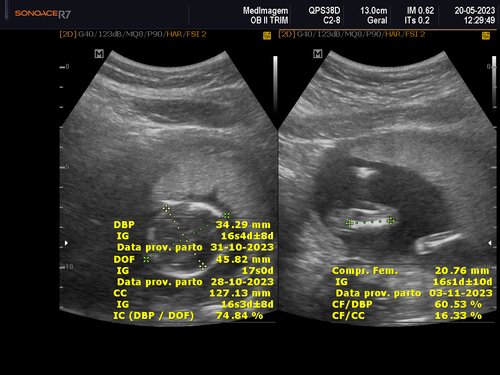

Eu tenho 27 anos estou grávida de 4 meses essa é a minha quarta gestação as minhas três últimas gestações eu perdi os bebês nunca consegui levar a gravidez adiante, eu quero muito conseguir levar essa, MINHA GRAVIDEZ É DE ALTO RISCO.

Uma amiga me deu a ideia de fazer uma vaquinha online, para conseguir fazer o tratamento no particular e o parto também, com ajuda de alguns amigos consegui arrecadar um valor e começar o tratamento no particular tive uma consulta com uma médica maravilhosa doutora Rochelle Hygino que na primeira consulta já me encaminhou para internação e para cirurgia, precisei fazer uma cerclagem no útero que é costurar o útero para segurar o bebê.